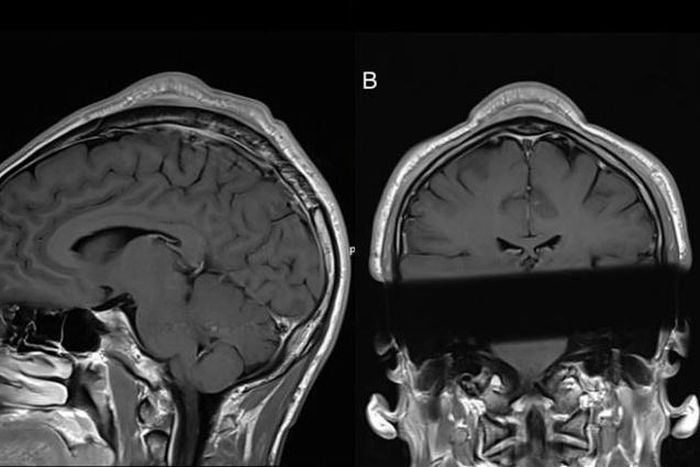

Ban đầu, các bác sĩ đã cân nhắc một số chẩn đoán có thể xảy ra, bao gồm cả việc khối phồng có thể là ung thư hoặc khối u lành tính. Chụp MRI cho thấy đó là thứ mà các tác giả của báo cáo ca bệnh gọi là "khối u dưới cơ Galeal có kích thước 34 cm x 0,6 cm x 2,9 cm gần đỉnh đường giữa".

Cuối cùng, các bác sĩ kết luận đó là một ví dụ cực đoan về cục u trên da đầu mà "headspin" có thể liên quan. "Trong các mô tả về X-quang, thuật ngữ 'cone-head sign' (dấu hiệu đầu hình nón) thường được sử dụng", các bác sĩ viết.